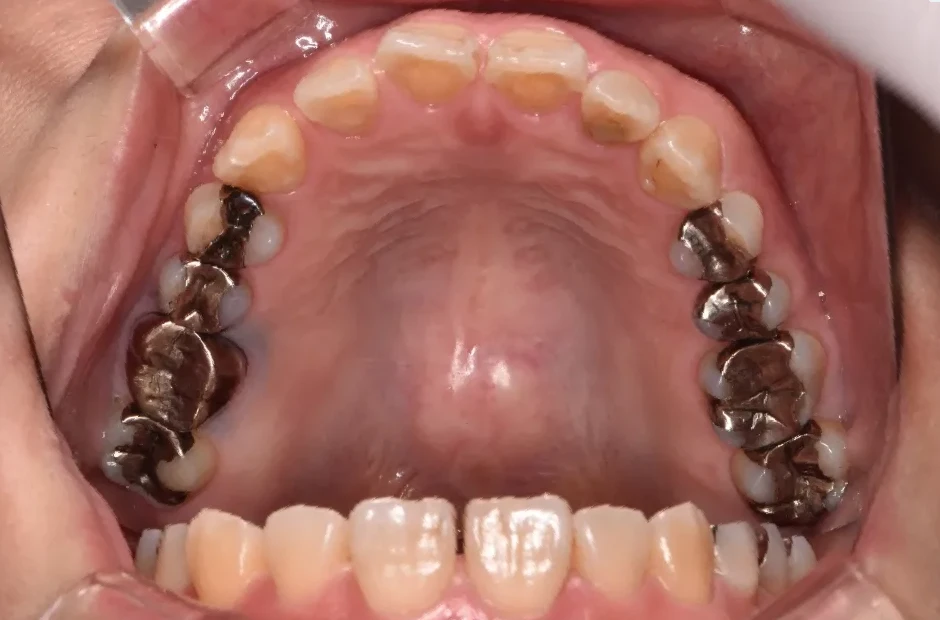

叢生

| 診断名・主訴 | 叢生 |

|---|---|

| 年齢・性別 | 43歳・女性 |

| 治療期間・回数 | 2年7か月 27回 |

| 治療に用いた主な装置 | 舌側矯正 |

| 抜歯部位 | 両顎4,4 |

| 治療費 | 100万円(税抜) |

| リスク・副作用 | 装置による違和感・疼痛・歯肉退縮・歯根吸収・虫歯のリスクなど |

治療前